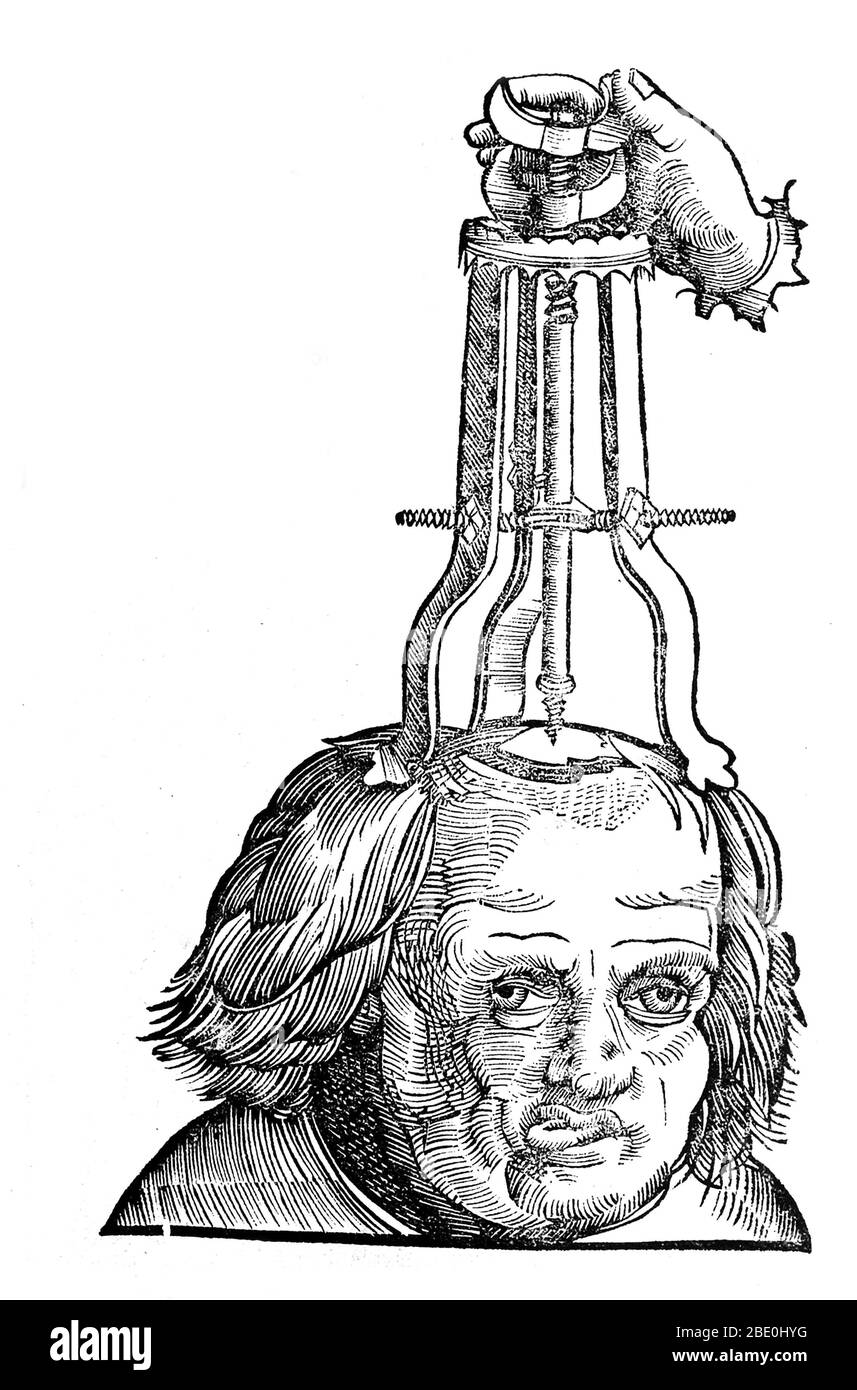

Removing the bone with a trochlea bipes, after trephination, 1527. Trepanning is a surgical intervention in which a hole is drilled or scraped into the human skull, exposing the dura mater to treat health problems related to intracranial diseases. Cave paintings indicate that people believed the practice would cure epileptic seizures, migraines, mental disorders and the bone that was trepanned was kept as a charm to keep evil spirits away. Trepanation was also practiced in the classical and Renaissance periods. Stock Photohttps://www.alamy.com/image-license-details/?v=1https://www.alamy.com/removing-the-bone-with-a-trochlea-bipes-after-trephination-1527-trepanning-is-a-surgical-intervention-in-which-a-hole-is-drilled-or-scraped-into-the-human-skull-exposing-the-dura-mater-to-treat-health-problems-related-to-intracranial-diseases-cave-paintings-indicate-that-people-believed-the-practice-would-cure-epileptic-seizures-migraines-mental-disorders-and-the-bone-that-was-trepanned-was-kept-as-a-charm-to-keep-evil-spirits-away-trepanation-was-also-practiced-in-the-classical-and-renaissance-periods-image352835070.html

Removing the bone with a trochlea bipes, after trephination, 1527. Trepanning is a surgical intervention in which a hole is drilled or scraped into the human skull, exposing the dura mater to treat health problems related to intracranial diseases. Cave paintings indicate that people believed the practice would cure epileptic seizures, migraines, mental disorders and the bone that was trepanned was kept as a charm to keep evil spirits away. Trepanation was also practiced in the classical and Renaissance periods. Stock Photohttps://www.alamy.com/image-license-details/?v=1https://www.alamy.com/removing-the-bone-with-a-trochlea-bipes-after-trephination-1527-trepanning-is-a-surgical-intervention-in-which-a-hole-is-drilled-or-scraped-into-the-human-skull-exposing-the-dura-mater-to-treat-health-problems-related-to-intracranial-diseases-cave-paintings-indicate-that-people-believed-the-practice-would-cure-epileptic-seizures-migraines-mental-disorders-and-the-bone-that-was-trepanned-was-kept-as-a-charm-to-keep-evil-spirits-away-trepanation-was-also-practiced-in-the-classical-and-renaissance-periods-image352835070.htmlRM2BE10ME–Removing the bone with a trochlea bipes, after trephination, 1527. Trepanning is a surgical intervention in which a hole is drilled or scraped into the human skull, exposing the dura mater to treat health problems related to intracranial diseases. Cave paintings indicate that people believed the practice would cure epileptic seizures, migraines, mental disorders and the bone that was trepanned was kept as a charm to keep evil spirits away. Trepanation was also practiced in the classical and Renaissance periods.

Removing the bone with a trochlea bipes, after trephination, 1527. Trepanning is a surgical intervention in which a hole is drilled or scraped into the human skull, exposing the dura mater to treat health problems related to intracranial diseases. Cave paintings indicate that people believed the practice would cure epileptic seizures, migraines, mental disorders and the bone that was trepanned was kept as a charm to keep evil spirits away. Trepanation was also practiced in the classical and Renaissance periods. Stock Photohttps://www.alamy.com/image-license-details/?v=1https://www.alamy.com/removing-the-bone-with-a-trochlea-bipes-after-trephination-1527-trepanning-is-a-surgical-intervention-in-which-a-hole-is-drilled-or-scraped-into-the-human-skull-exposing-the-dura-mater-to-treat-health-problems-related-to-intracranial-diseases-cave-paintings-indicate-that-people-believed-the-practice-would-cure-epileptic-seizures-migraines-mental-disorders-and-the-bone-that-was-trepanned-was-kept-as-a-charm-to-keep-evil-spirits-away-trepanation-was-also-practiced-in-the-classical-and-renaissance-periods-image352826644.html

Removing the bone with a trochlea bipes, after trephination, 1527. Trepanning is a surgical intervention in which a hole is drilled or scraped into the human skull, exposing the dura mater to treat health problems related to intracranial diseases. Cave paintings indicate that people believed the practice would cure epileptic seizures, migraines, mental disorders and the bone that was trepanned was kept as a charm to keep evil spirits away. Trepanation was also practiced in the classical and Renaissance periods. Stock Photohttps://www.alamy.com/image-license-details/?v=1https://www.alamy.com/removing-the-bone-with-a-trochlea-bipes-after-trephination-1527-trepanning-is-a-surgical-intervention-in-which-a-hole-is-drilled-or-scraped-into-the-human-skull-exposing-the-dura-mater-to-treat-health-problems-related-to-intracranial-diseases-cave-paintings-indicate-that-people-believed-the-practice-would-cure-epileptic-seizures-migraines-mental-disorders-and-the-bone-that-was-trepanned-was-kept-as-a-charm-to-keep-evil-spirits-away-trepanation-was-also-practiced-in-the-classical-and-renaissance-periods-image352826644.htmlRM2BE0HYG–Removing the bone with a trochlea bipes, after trephination, 1527. Trepanning is a surgical intervention in which a hole is drilled or scraped into the human skull, exposing the dura mater to treat health problems related to intracranial diseases. Cave paintings indicate that people believed the practice would cure epileptic seizures, migraines, mental disorders and the bone that was trepanned was kept as a charm to keep evil spirits away. Trepanation was also practiced in the classical and Renaissance periods.